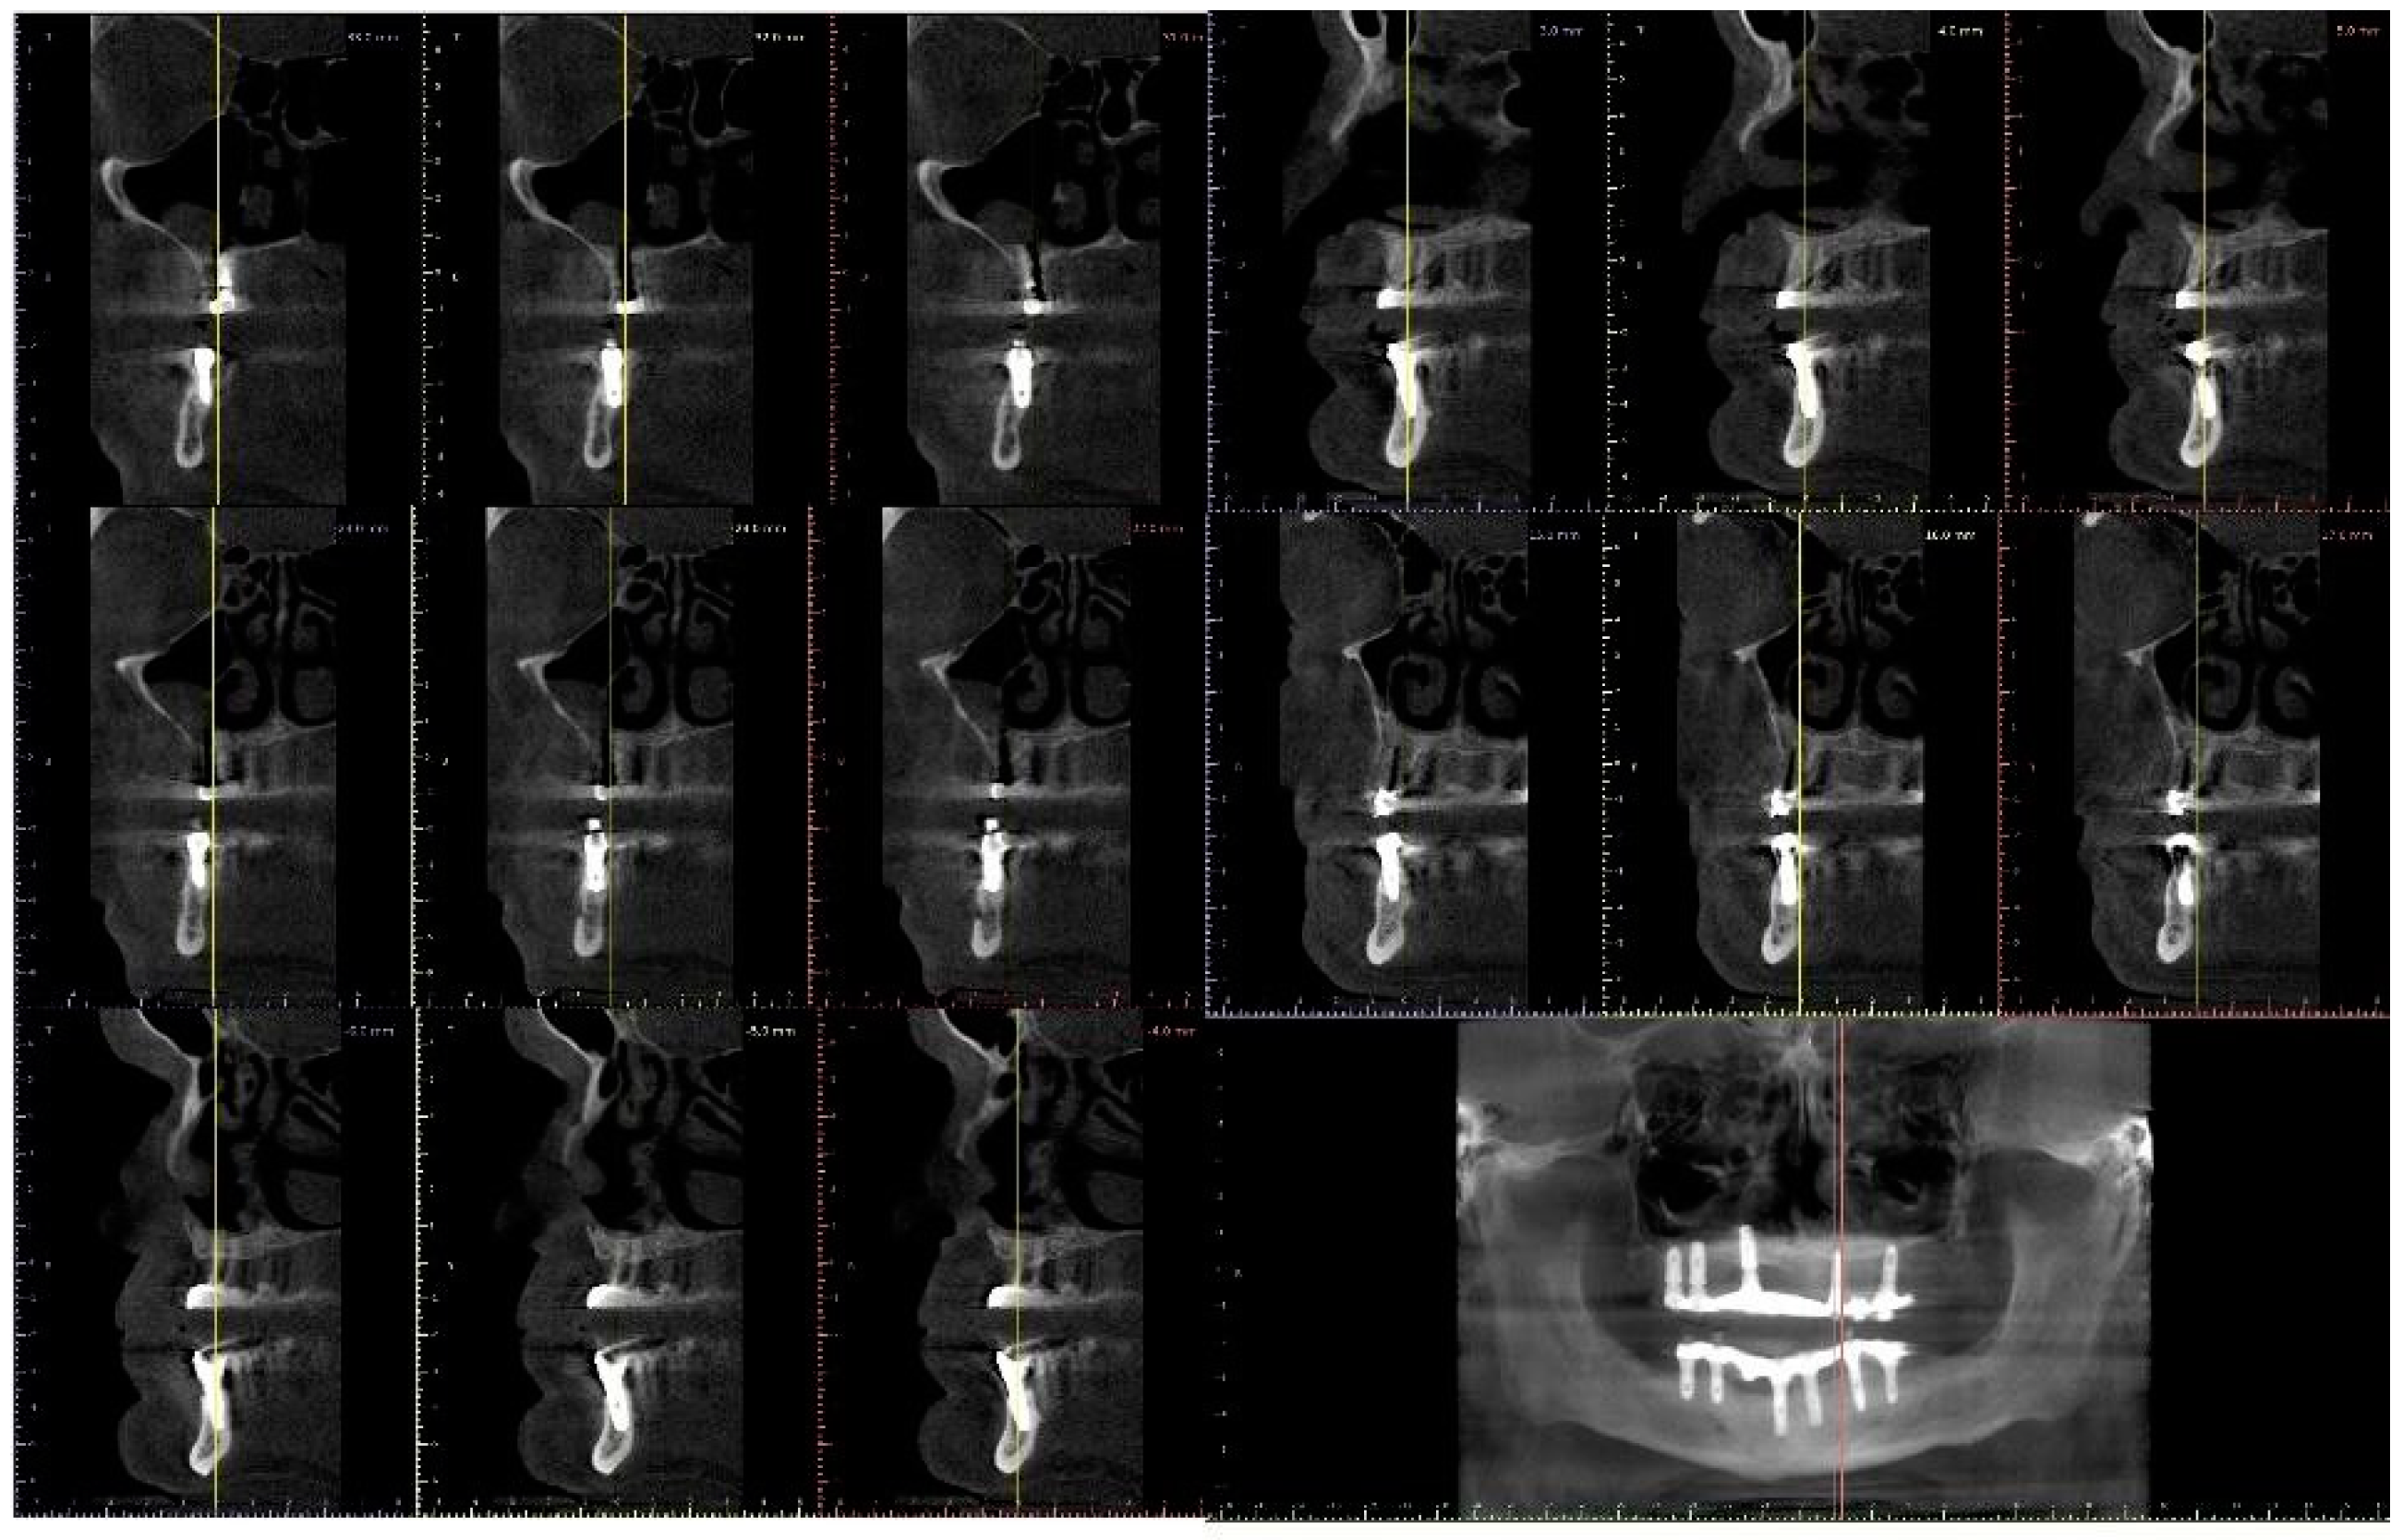

| Flanagan D. et al. [23] | J Oral Implantol | 2015 | clinical and radiographic: full-mouth radiographic series, panoramic and a bimaxillary cone beam computerized scan and mounted study casts | -One patient | Subject of 34 yo male; severely carious teeth and associated chronic abscesses (kidney transplant delayed) Comorbidities: IgA nephropathy, tabagism, hypertension and secondary hyperparathyroidism. Hemodialysis three times weekly. Ph. Therapy: Nephrocaps vitamin (B) supplement, amlodepine, besylate, cinacalcet, metoprolol, paroxetine. Bilateral compound ulnar and radial fractures, 2 blood transfusions. | Successfully treated with dental implant-supported fixed prostheses: fixed bimaxillary porcelain fused to metal implant-supported complete dentures |

| Flanagan D. et al. [23] | J Oral Implantol | 2015 | -Implant treatment for patients with IgA nephropathy (secondary hyperparathyroidism and osteodystrophy) may be successful. -Appropriate calcium therapy is important serum calcium to prevent inappropriate bone remodeling | 2 years | Long-term dialysis patient with end-stage renal disease (ESRD)also referred to as chronic kidney disease (CKD) due to IgA nephropathy complicated by severe secondary hyperparathyroidism and renal osteodystrophy | |